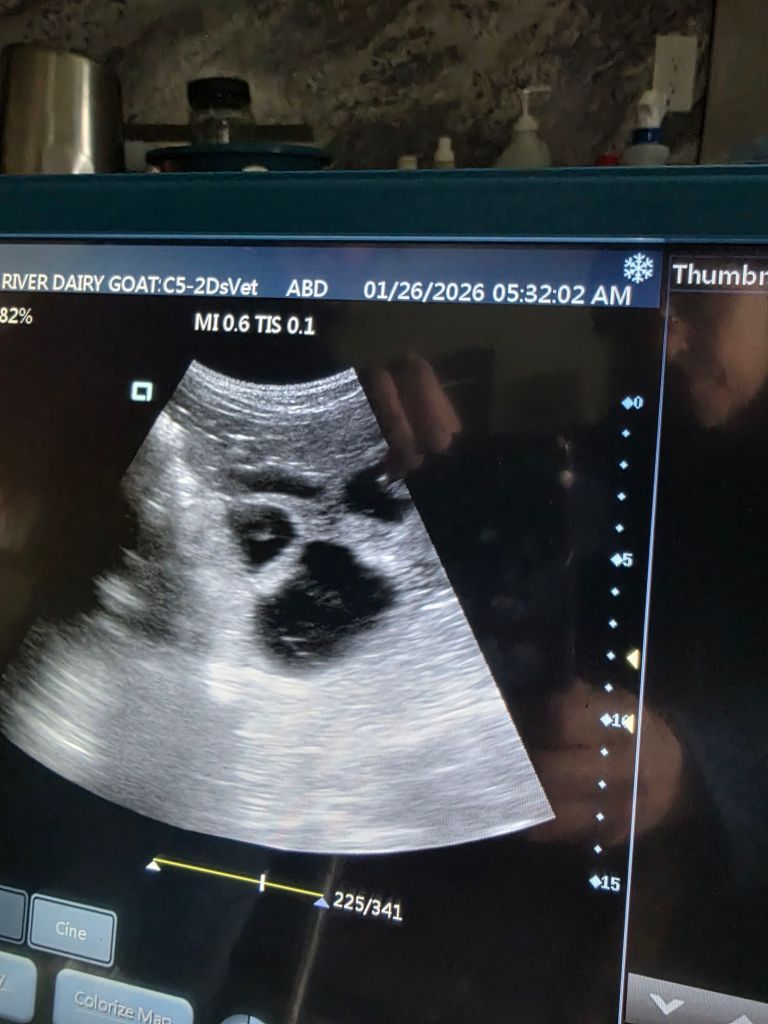

January 26, 2026

Ultrasounds are completed